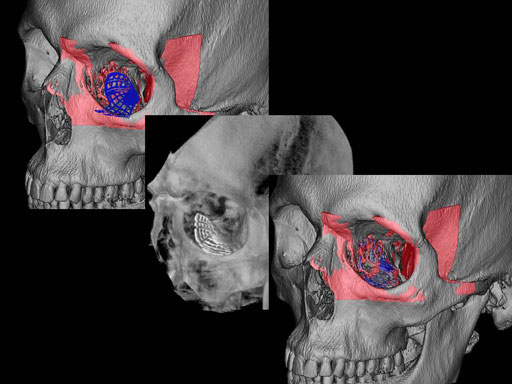

Furthermore, as orbital floor fractures are quite frequently associated with medial wall fractures; anatomic restoration especially in the transition zone between both wall is a demanding procedure. As described by B. Hammer, the orbital floor has an initial shallow convex section behind the rim, then inclines upward behind the globe, and inclines upward to meet the medial wall, creating a distinct bulge behind the globe. These convex curves of the medial wall and floor create a postbulbar constriction of the orbital cavity, which must be reconstructed when the orbit is rebuilt following fractures. Treatment is directed at precise anatomical reconstruction of orbital shape and volume in order to restore the correct position of the eye. To provide surgeons with an adequate implant that addresses the requirements of two wall acute orbital fractures or for secondary reconstruction of enophthalmos and dystopia, a new series of preformed orbital plates was developed for the new orbital matrix system.

Unlike the existing two-dimensional mesh implants, the geometry of the new preformed plates will be adequate to match the individual anatomic situation of the patient in almost any case. However, the mesh parts can be individually adjusted if necessary. In these cases the solid part in the central posterior area needs to remain untouched. Areas of the orbit that do not require a bridging can be spared out by trimming the implant along the designated cutting lines in the height of the medial wall and/or length of the orbital floor area. The lateral anterior part of the plate is intentionally pre-bent higher than the orbital rim anatomy to allow free plate movement during plate positioning.

The Preformed Orbital Plates are indicated for trauma repair and reconstruction of fractures of the orbital floor, medial orbital wall or combined fractures of floor and medial wall. It should be noted that in three-wall fractures where the lateral wall is also involved, a second orbital implant, ( i. e. the mesh plate) must be used in addition to the pre-formed orbital plate.

Implant placement according to the orbital landmarks

1 Orbital rim, 2 Inferior orbital fissure, 3 Posterior orbital ledge, 4 Transition between the medial wall and orbital floor, 5 Optic canal, 6 Lacrimal fossa